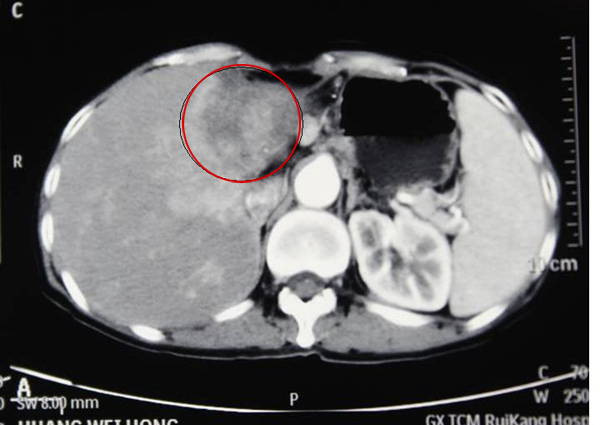

去年7月,在腹痛加重一个月后,经熟人介绍,黄女士来到了瑞康医院肿瘤二区,检查发现她患上的是一种恶性程度非常高的肝内胆管细胞癌。通过手术难以完全切除,即使勉强切除,也有很大可能复发,还容易引发起肝功能衰竭等严重并发症。手术疗效不好,这种癌对化疗药物的敏感性也相当差,可是如果不采取治疗,病情很快会恶化。黄女士将进入6个月极为痛苦的生命倒计时。

黄女士治疗前肝肿瘤(红圈内)